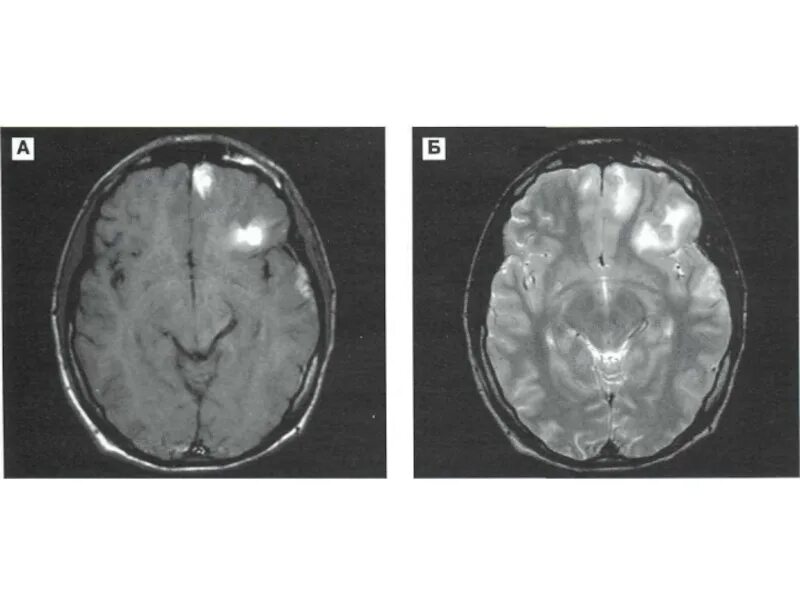

Диффузной биполушарной кортикальной атрофии